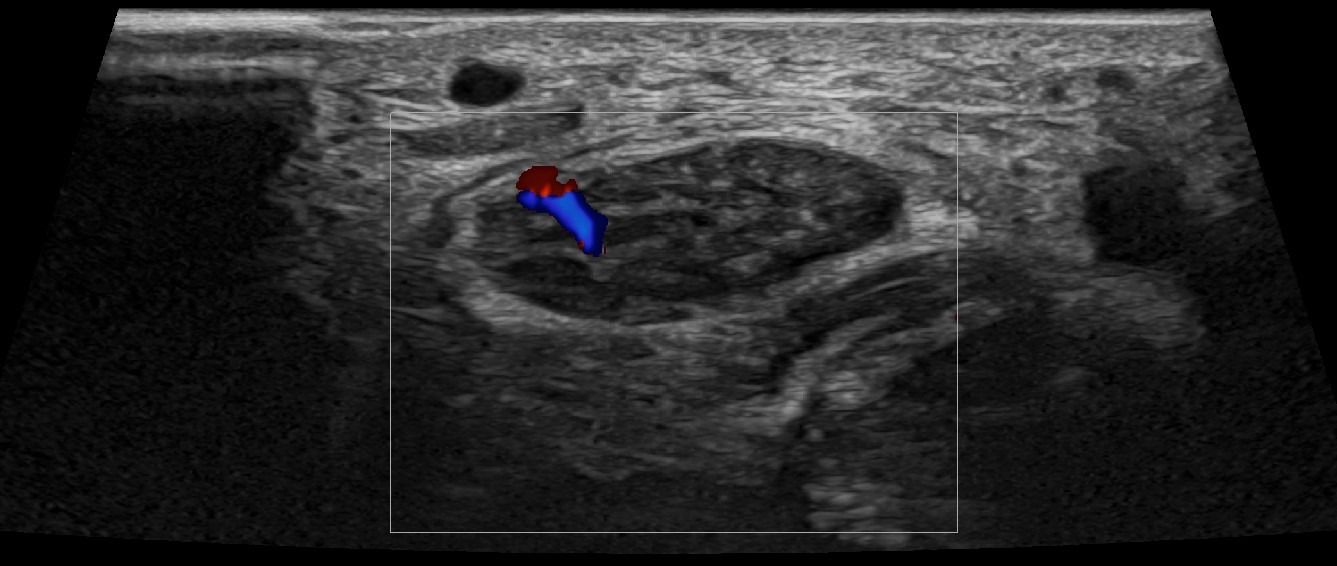

- Focal Lesions (tumors, neuromas)